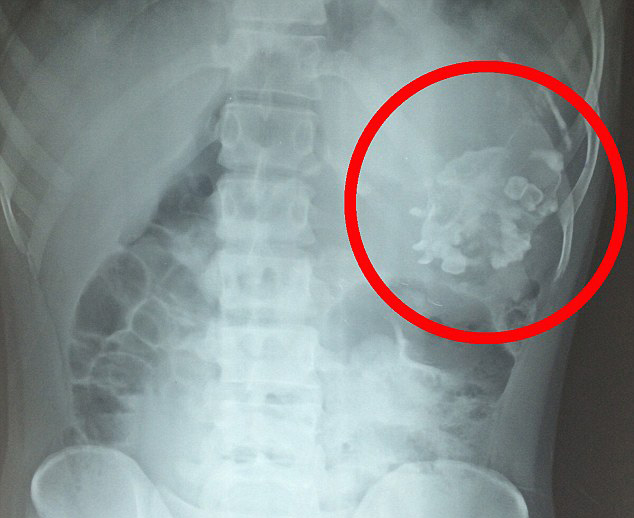

Gencin karnında 2.5 kg ağırlığında kemik, saç ve dişlerden oluşan kütle bulan doktorlar hayretler içinde kaldı. Parazit ikizin, 18 yıl boyunca göbek bağı sayesinde Narendra'nın vücudundan beslendiği ortaya çıktı. Narendra'ya, dünyada şu ana kadar 200 hastada tespit edilmiş 'cenin içinde cenin' teşhisi kondu.

Bu olay, ikiz hamileliğin erken dönemlerinde, bir fetüsün göbek bağı yoluyla diğer fetüse girmesi olarak açıklanmakta. Bu tarz vakalarda parazit fetüs, kardeşinin bedeninden beslenerek hayatta kalmakta.